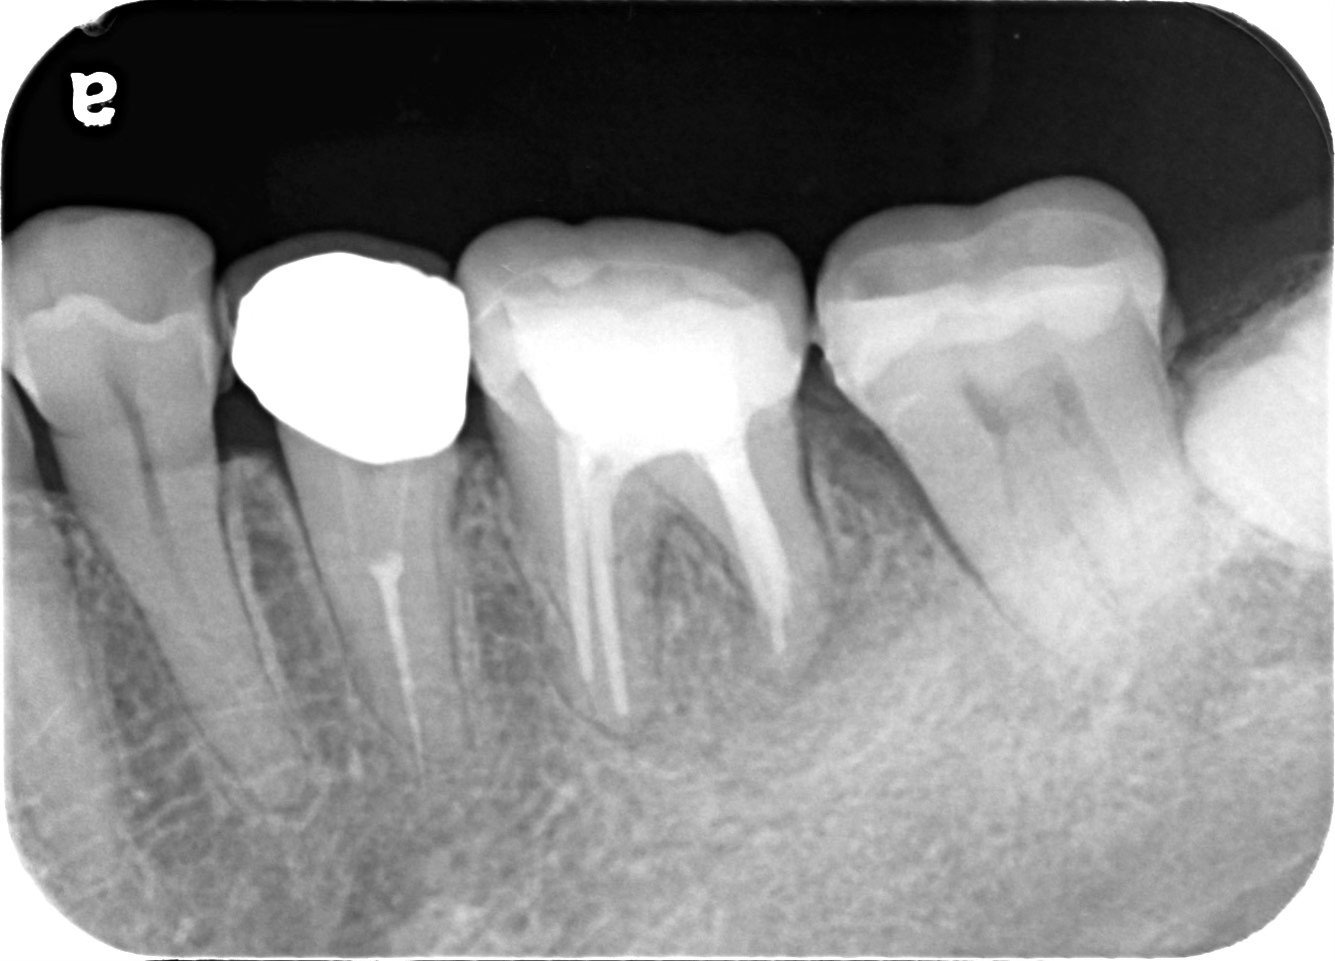

こちらは、同じ部位をCTとレントゲンで撮影したものを比較した画像です。

• 比較

左側はCT画像、右側はレントゲン画像です。赤丸で示した部分に黒い影が確認できますが、これが炎症の起きている部位です。

CTでは確認できますが、レントゲンでは写らず、見落とされることがあります。

レントゲンのみで診断した場合、この炎症に気付かないまま進行し、結果として抜歯に至るケースもあります。

当院ではそのリスクを避けるため、CTによる診断を徹底しています。